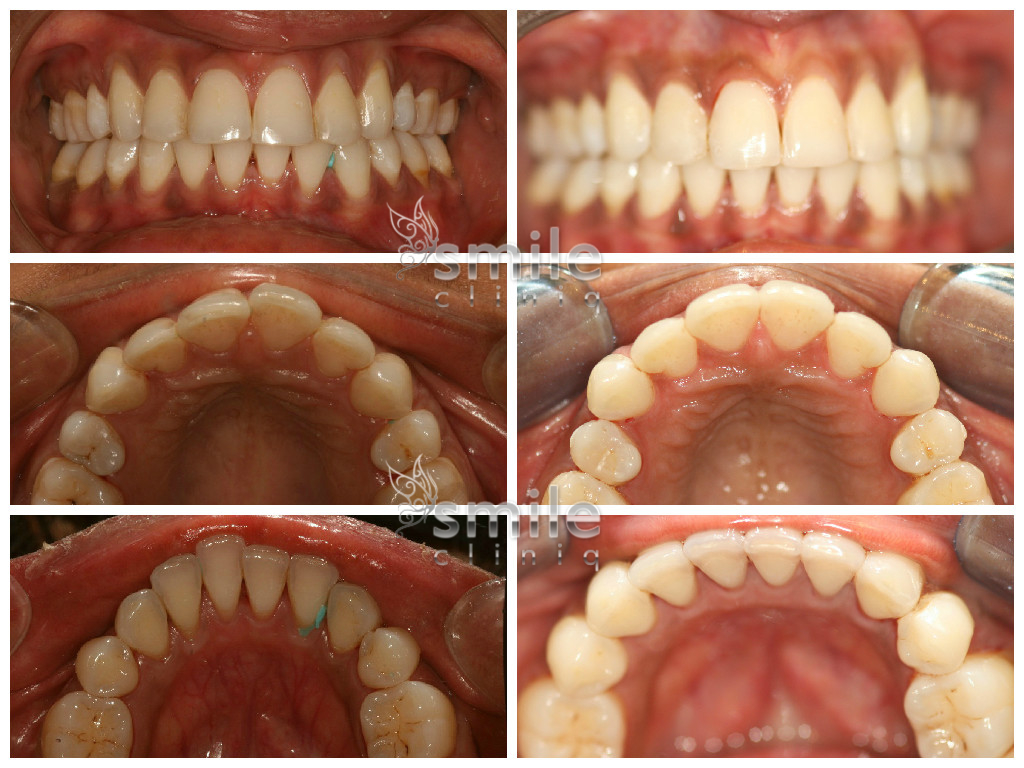

Before and After Gallery

Invisalign – Invisible Braces Before

Before

Invisalign – Invisible Braces After

After

Please scroll below for some of our past Invisalign cases: